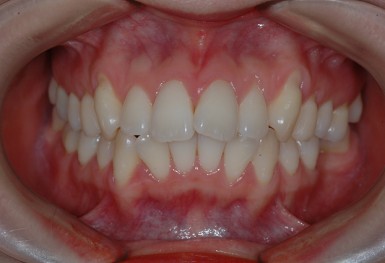

심한 덧니